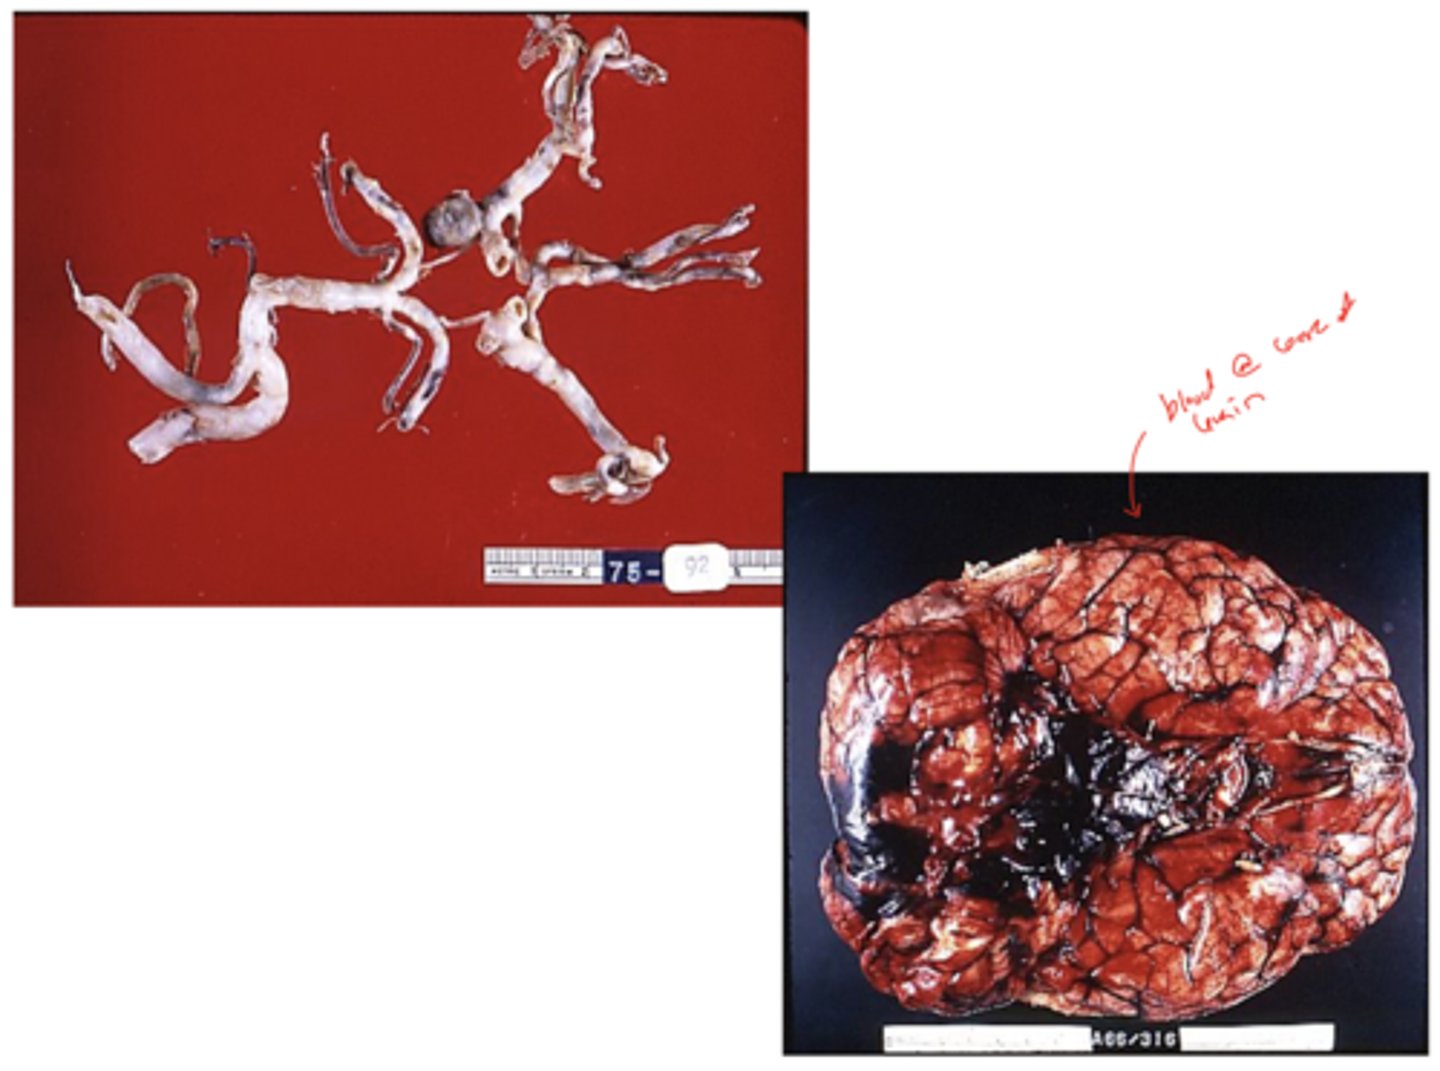

hypertensive small vessel disease:

dilation and thickening of the arteriole wall -> "Charcot-Bouchard aneurysms"

non-traumatic subarachnoid hemorrhage (SAH)

SAH: